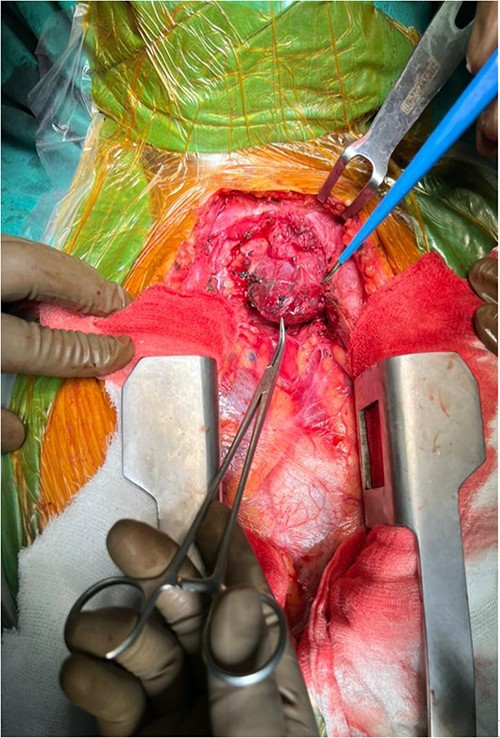

A 57-year-old female came with chest discomfort and cough since 1 month. The chest X-ray (Fig. 1) showed mass in the superior mediastinum. CECT thorax (Fig. 2) revealed the soft tissue density 7 cm × 7 cm (Fig. 3) in superior mediastinum abutting subclavian artery, azygous vein, anteriorly displacing superior venacava, anteromedially abutting arch of aorta, posteromedially compressing trachea and abutting right main bronchus. A 4.9 cm × 5 cm mass in the left side superior mediatinum was seen abutting internal jugular vein and brachiocephalic artery. USG showed the presence of normal thyroid in the neck. CT guided biopsy from the right mass showed ectopic thyroid tissue (ETT)-colloid goiter. Due to close proximity with major vessels sternotomy done. Mass in the left side 5 cm × 5 cm (Fig. 4) in the superior mediastinum was identified, on dissecting superiorly, which was free from the thyroid in the neck and abutting the IJV, brachiocephalic artery and left innominate vein that were separated with meticulous dissection.

The right mass (Fig. 5) was even bigger and needed an extension of incision into the neck (Fig. 6). About 7 cm × 7 cm noted to be displacing Superior venacava anteriorly that was dissected from it, separated from the first rib and subclavian artery meticulously taking care not to damage any major structure. Both masses were excised. These masses were not connected in any way with each other as well as with the orthotopic thyroid in the neck. Post-op was uneventful. Thyroid functions were normal. Thyroid scan (Fig. 8) showed no evidence of a thyroid tissue in the mediastinum and no other ectopic thyroid was present other than the orthotopic thyroid tissue in neck. The patient was discharged on POD 10 without any symptoms. The histopathological tissue diagnosis showed a colloid goiter (Fig. 7). All data kept in our database.